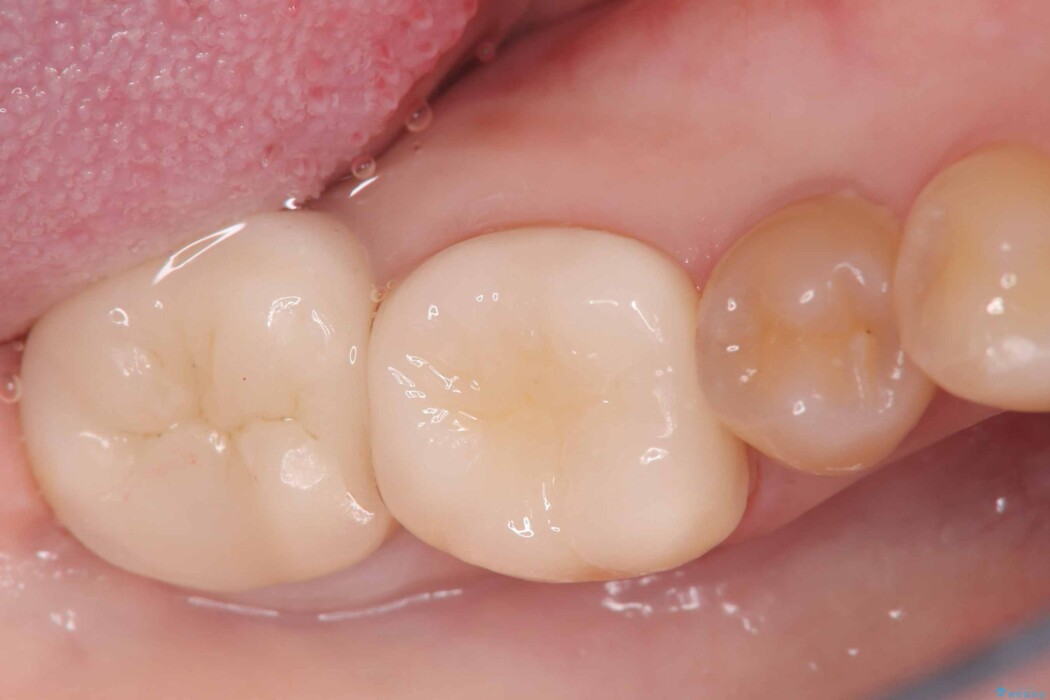

今回は歯の強度と将来的な破折リスクを考慮し、セラミッククラウンによる治療を行うこととしました。

治療後について

クラウンにすることで、歯全体を保護しながら、見た目も自然で長期的に安定した状態を維持しやすくなります。